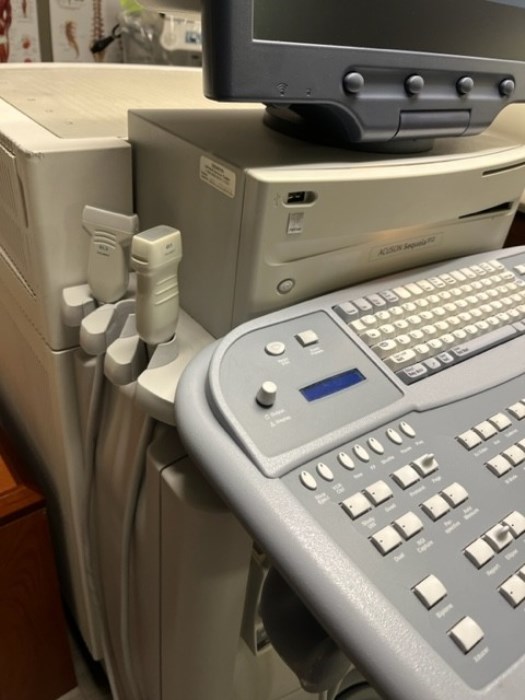

Siemens Sequioa Ultrasound

Pre-owned. In good working condition. Shown as is. Siemens Sequoia Ultrasound. DOM: 2006

Probes: 15L8w, 4V1, 10V4, 6L3, 4C1